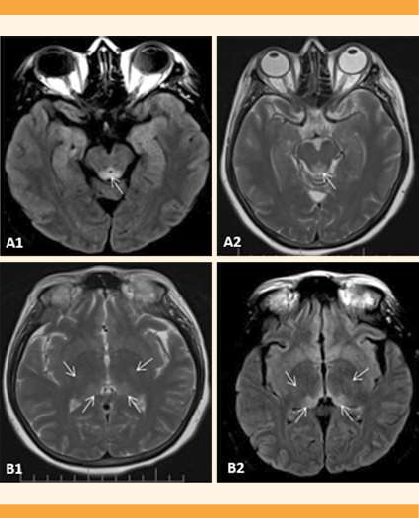

De acuerdo con la evolución clínica de la paciente y su estado gravídico, se sospechó trombosis de senos venosos, por lo que se inició tratamiento con anticoagulantes. La angiorresonancia y resonancia magnética cerebrales evidenciaron lesiones hiperintensas en T2 y FLAIR, en las regiones talámica bilateral, periacueductal mesencefálica y los ganglios basales bilaterales, además de disminución del flujo en los senos venosos profundos (Figura 2), por lo que requirió panangiografía para la tipificación de la lesión. En consenso con el servicio de Neurología y considerando el antecedente de hiperémesis gravídica con alteración de la concentración de sodio y potasio, con velocidad de reposición de electrolitos no clara, se concluyó que el cuadro era compatible con mielinolisis extrapontina.

Figura 2 Resonancia magnética cerebral que muestra lesiones hiperintensas de la sustancia blanca profunda de forma simétrica, periventriculares y periacueductales. A1) Cortes en T2. A2) (FLAIR) se observan lesiones hiperintensas en el tegmen mesencefálico. B1) Cortes en T2 y B2) (FLAIR) lesiones en la región posteromedial y posterolateral del tálamo.